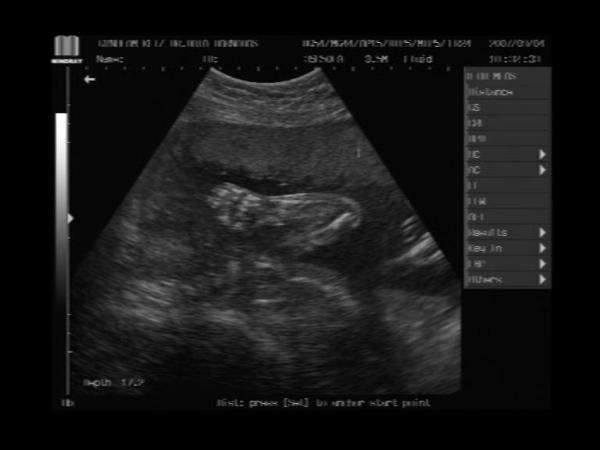

És a bébi 24 hetesen:

Kép És a kis kezecskéje...